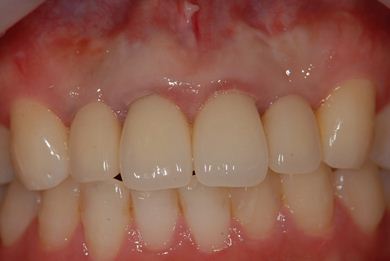

治療後

• 治療後